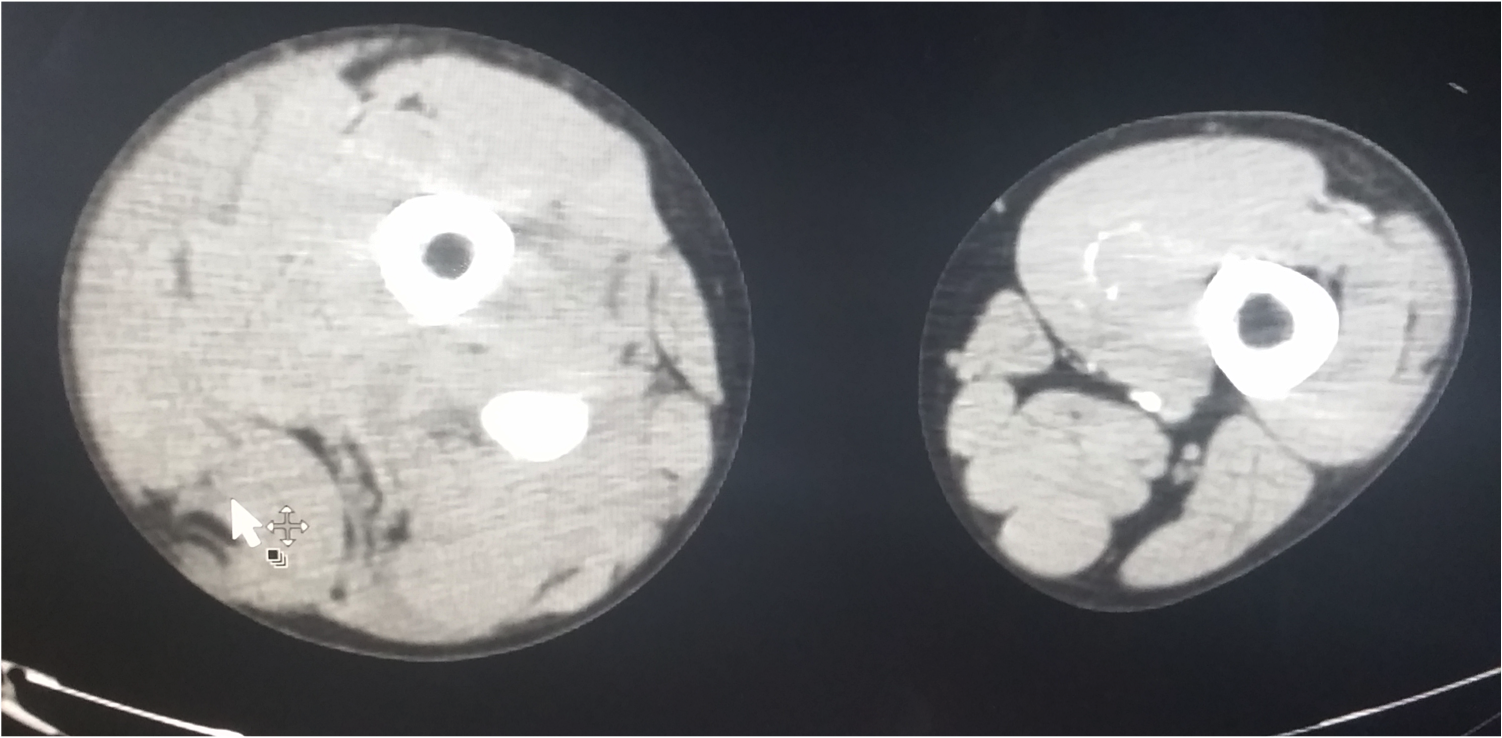

CTA of Lower Extremities

19 y/o M no PMH BIBEMS s/p being struck by garbage truck. Concern for massive bleeding into R thigh compartment, w/ distal extremity hypoperfusion. Pelvis bound, MTP initiated, TXA given. Intubated due to waxing/waning comprehension. Portable pelvis films w/o pelvis or femur fracture. Hypotensive in CT scanner, push-dose pressors given. CT showing popliteal artery injury. Taken to OR.